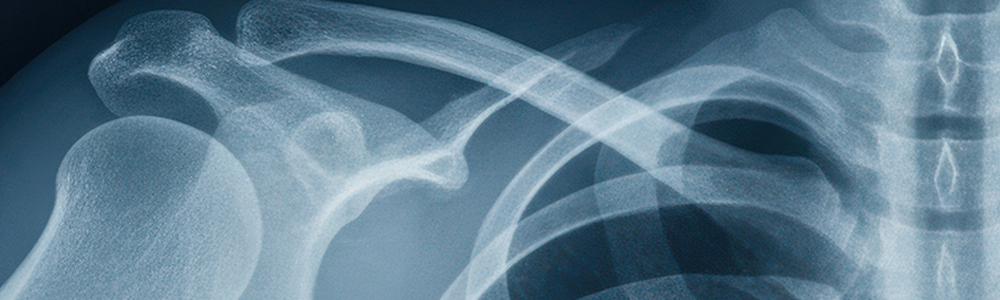

Röntgen des Bewegungsapparates

Für die bildliche Darstellung des Bewegungsapparates oder einzelner Gelenke ist das Röntgen das Standardverfahren der Orthopädie. Brüche, Fehlstellungen und Verschleißerscheinungen können so am besten festgestellt werden.

Während der Röntgenuntersuchung wird der Patient so gelagert, dass die Röntgenstrahlen der Apparatur durch seinen Körper hindurch dringen können und auf einen Röntgenfilm abgebildet werden. Da die Röntgenstrahlen unterschiedlich stark von den Knochen und Organen absorbiert werden, entsteht ein negatives schwarz-weiß Bild des Körpers, anhand dessen die Beschaffenheit der Knochen und Organe genau beurteilt werden kann. Die Aufnahme des Röntgenbildes dauert nur wenige Sekunden und der Patient spürt nichts.